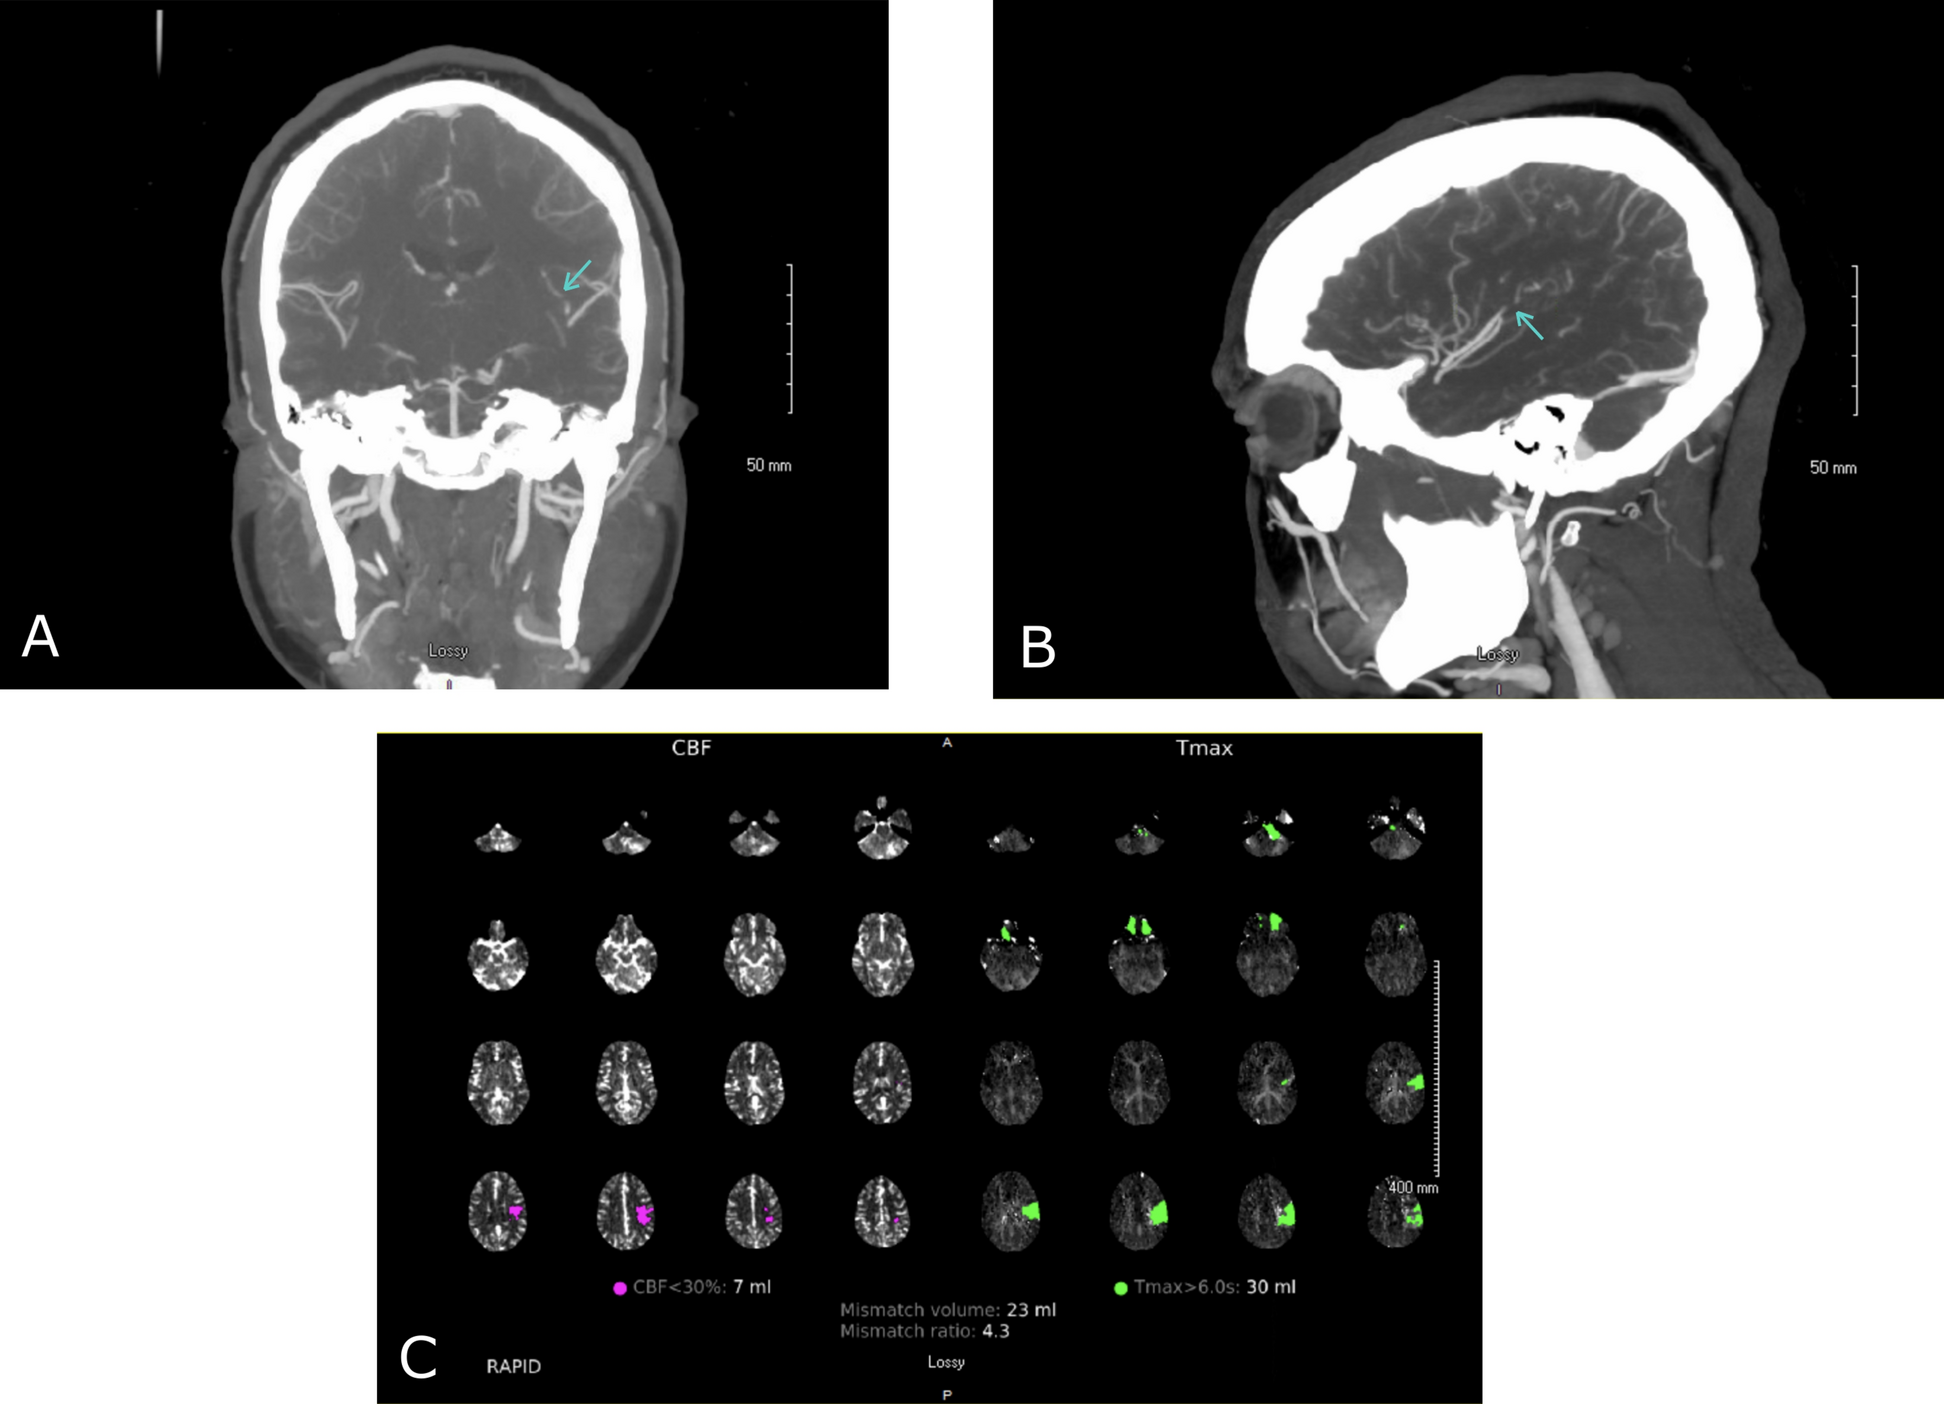

In our patient, the evidence of EBV-positive lymphoid proliferation raised the question of a potential association between viral infections and AIS, especially given the patient’s young age and absence of other major risk factors for ischemic…

Acute ischemic stroke in a young adult in association with Epstein–Barr virus infection: a case report | Journal of Medical Case Reports